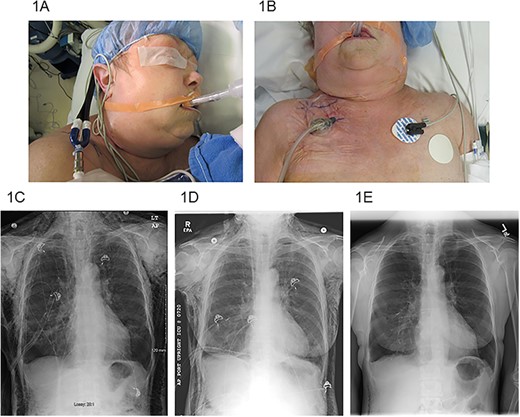

A 5-cm incision was made 2 cm below the clavicle on the ipsilateral side of the thoracic procedure under local anesthesia at the bedside. The incision was deepened through both the subcutaneous tissue and the pectoralis major fascia. Frequently, bubbling was encountered in the wound as the subcutaneous tissues started immediately decompressing. A black wound VAC sponge was cut to size and placed within the wound (Fig. 1A and B). The included plastic sheeting was used to form an adequate seal and suction was applied to −125 mm Hg (V.A.C.ULTA™ system while in-patient, then switched to the ACTIV.A.C.™ system at discharge, KCL/3M, 3M Center, St Paul, MN 55144-1000, USA). Once the wound VAC was placed it was very well tolerated, and only minimal pain medication was required. Sponge and dressing changes were performed twice a week until removal. After the SE had resolved, the wound VAC was removed in the clinic. Upon removal, nice granulation tissue was present and the wound was loosely adapted by interrupted sutures. All wounds healed without complications and the sutures were removed 7–10 days later.

(A) SE extending to the periorbital region, (B) right infraclavicular incision location with VAC dressing, (C) pre-operative chest X-ray, (D) chest X-ray post-operative day #3 after VAC placement and (E) chest X-ray post-operative day #22 after VAC placement.

Three of the patients were male and two were female. The median age was 68 years (range 61–70). All patients had an extensive smoking history. All patients were treated with VATS resections: one wedge resection, one lobectomy, two combined lobectomy and wedge resections for NSLC, and one thymectomy with extensive adhesiolysis for a thymoma. Chest tubes were routinely placed on −20 cm H2O suction post-operatively. Initial efforts at management of SE included both increase in chest tube suction (range 25–40 cm H2O) and slight withdrawal of the chest tube (range 2–5 cm). The VAC dressing was placed a median of 6 days after the initial operation (range 3–19 days). Median overall length of stay was 16 days (range 7–23). Median length of VAC treatment was 10 days (range 4–15). All patients had immediate improvement in symptoms and quick resolution of SE by the VAC dressing therapy (Fig. 1C–E). All patients were successfully discharged home. One patient was discharged without a chest tube or VAC therapy, one patient required a chest tube with Heimlich valve, two patients required only VAC therapy, and one patient required both VAC therapy and chest tube with Heimlich valve at discharge. No complications of incision or VAC dressing placement were observed.